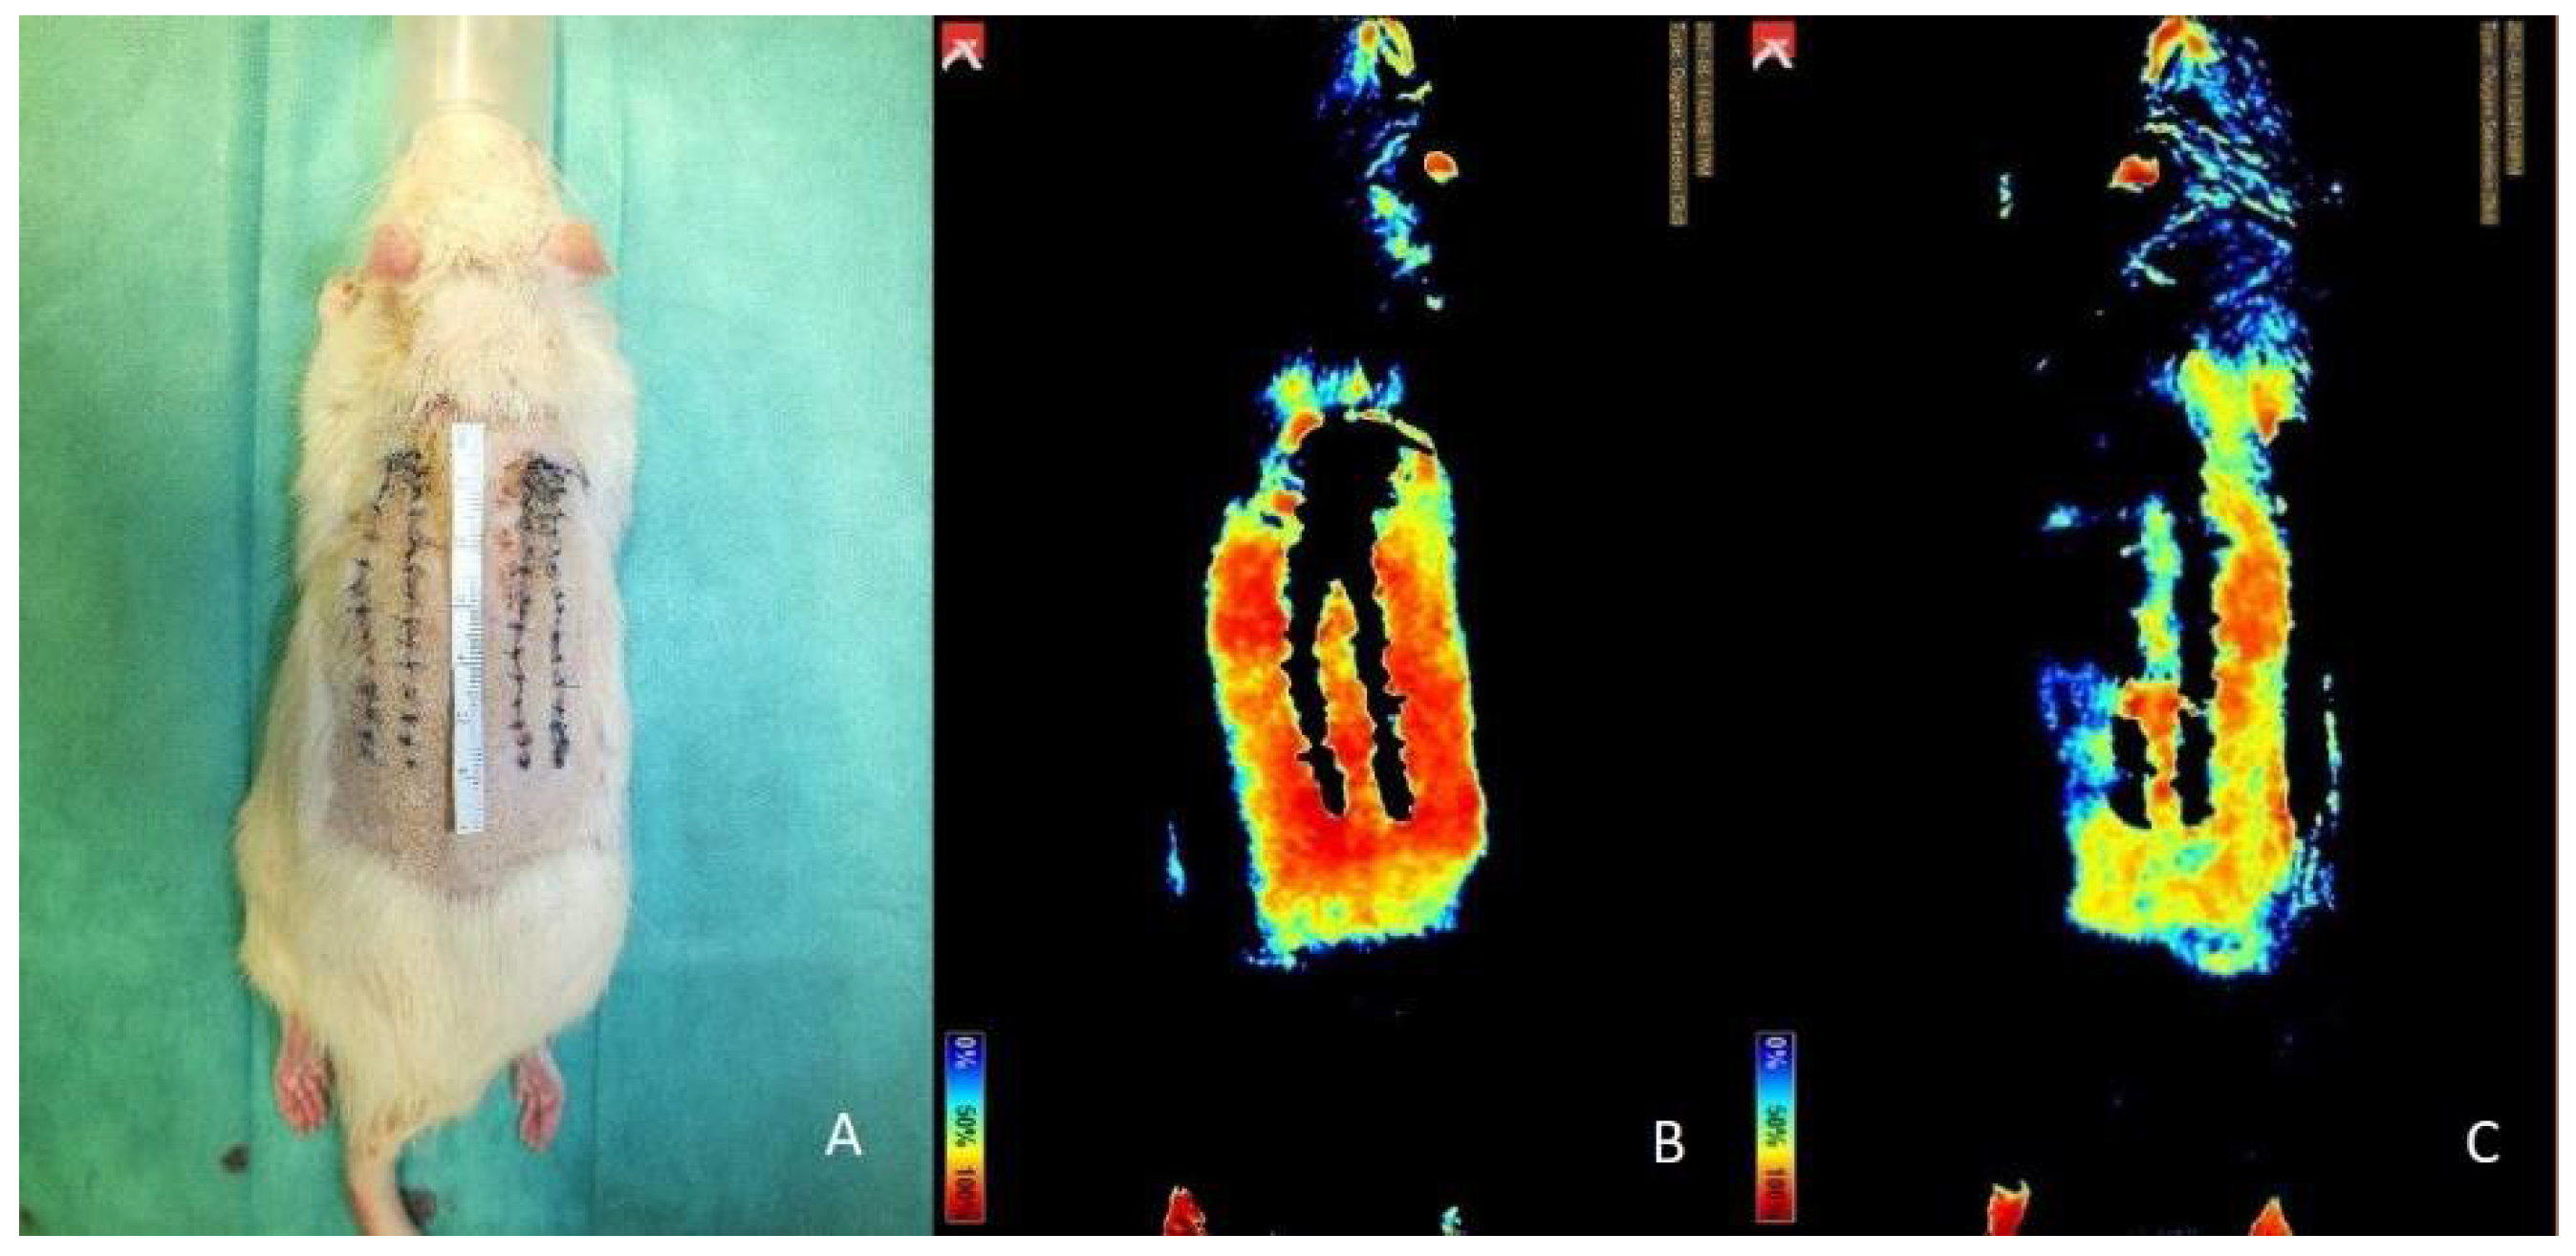

3.5. Near-Infrared Reflectance-Based Imaging and Infrared Thermography